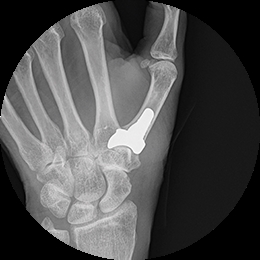

Three months after my wife had two titanium cervical discs implanted

in Germany, she was diagnosed with bilateral thumb joint

deterioration—a rare condition. I still remember a staff member’s

stunned reaction: “Both hands?!”

All because of the hell the Generic Drug Levofloxacin released on

her. To keep her thumbs

in place, she had to wear rigid shell braces. Now, I always move

fast which upsets opportunists, especially when it comes to

research—especially for her. Back in 2014, I’d confirmed that

Germany was leading innovation in spinal implants. An ER physician

told us then, “Most cutting-edge medical devices come from Germany.”

While researching thumb implants, I found something surprising: the

U.S. was ahead. I found a titanium thumb implant I trusted and

scheduled a consultation. Strangely, the surgeon recommended we look

to Europe. I pushed back: “No, America’s is ahead in thumb implants.

I called the manufacturer directly. They connected us with a

specialist in Raleigh, North Carolina. The surgeon was stunned.“You

contacted the manufacturer yourself?”I thought: Doesn’t everyone?

August of

2018: My wife received her First Titanium Surgical Thumb

Joint Implanted.

My wife has

her Second Titanium Surgical Thumb Joint Implanted.